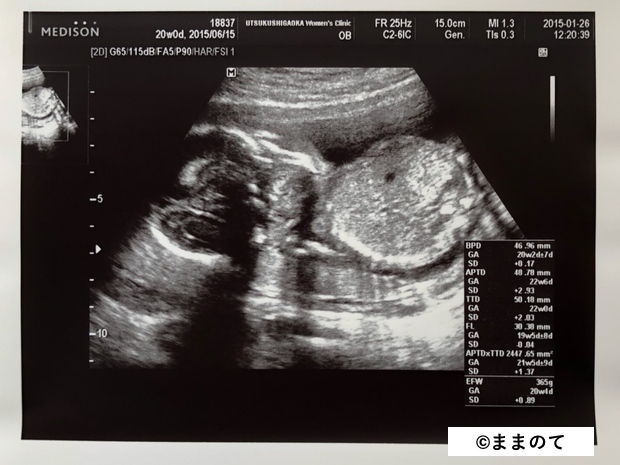

妊娠6ヶ月(20・21・22・23週)

赤ちゃんの骨格や顔立ちがしっかりしてきます。羊水を飲んで呼吸の練習を開始します。心臓が完成してくるため、エコー写真には心臓の弁の動きがはっきりと写し出されます。

身長は約30cm、体重は600~650gほどです。まだ脂肪は多くありませんが、3Dエコーや4Dエコーで全身が見られる時期のため、記念に受診する人もいるようです。

上のエコー写真では、股間からおちんちんが出ているのが見え、男の子だということがわかります。